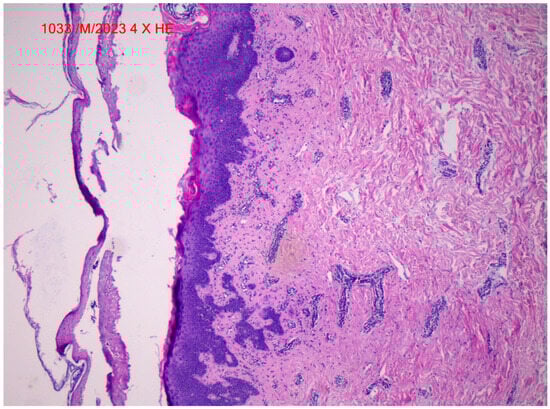

2. Case Report